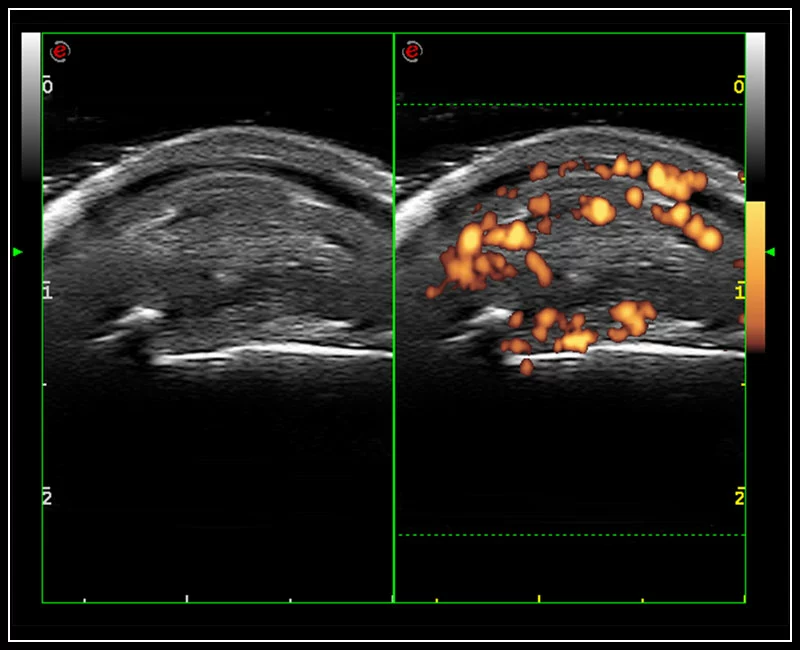

MyLab™9 Platform - High resolution imaging in testis

MyLab™9 Platform - High resolution imaging in testis

MyLab™9 Platform - XFlow in testis vascularization

MyLab™9 Platform - XFlow in testis vascularization